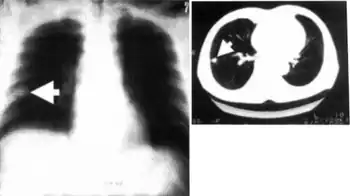

Chest image of individual with pulmonary dirofilariasis, solitary nodule called “coin lesion” is adjacent to the pleural membrane

Dirofilariasis is often diagnosed by the examination of tissue obtained as part of the diagnostic investigation of coin lesions. Blood tests are not yet helpful in the diagnosis of dirofilariasis in humans.[4]